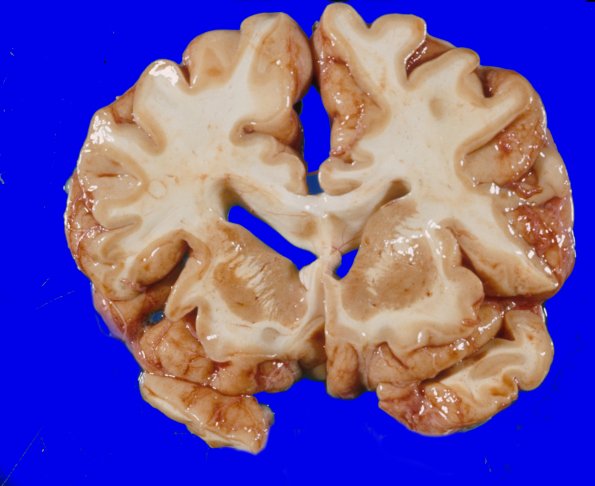

Coronal sections of the cerebral hemispheres and deep gray nuclei appear atrophic with dilatation and blunting of the lateral ventricles.